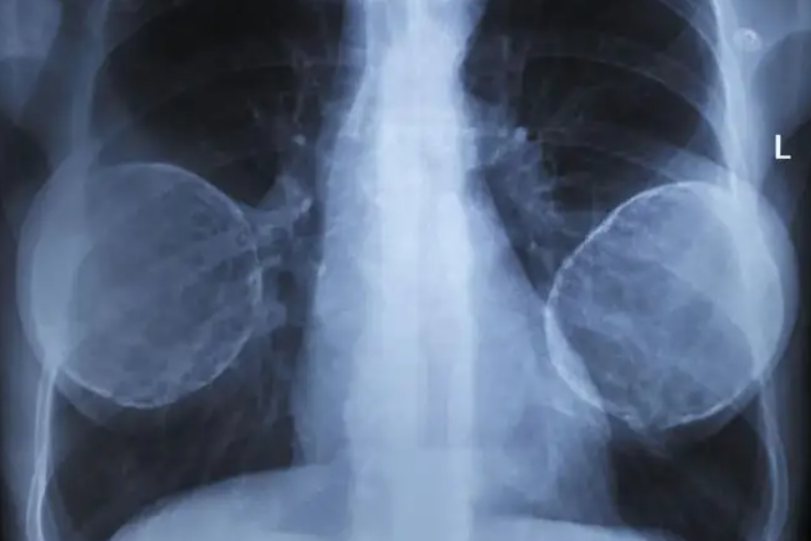

由于一般用于隆胸的假体密度高于自身组织密度,所以在胸透中会呈现高密度的阴影,可以很明确地看出受检者置有隆胸假体。

用于隆胸的假体类型较多,在临床中常用的有:硅胶、外阀性毛面双层假体、毛面硅凝胶假体、膨体假体等。

隆胸使用的假体大多数为医用硅凝胶囊,分为毛面性和滑面型两种。性质稳定,无毒,无致癌致畸性,很少发生排异反应,质地柔软,极易雕刻,不满意也可以完整取出假体,可以在体内长期置放。另外还有生理盐水假体和水凝胶假体,可根据受术者自身情况进行选择。